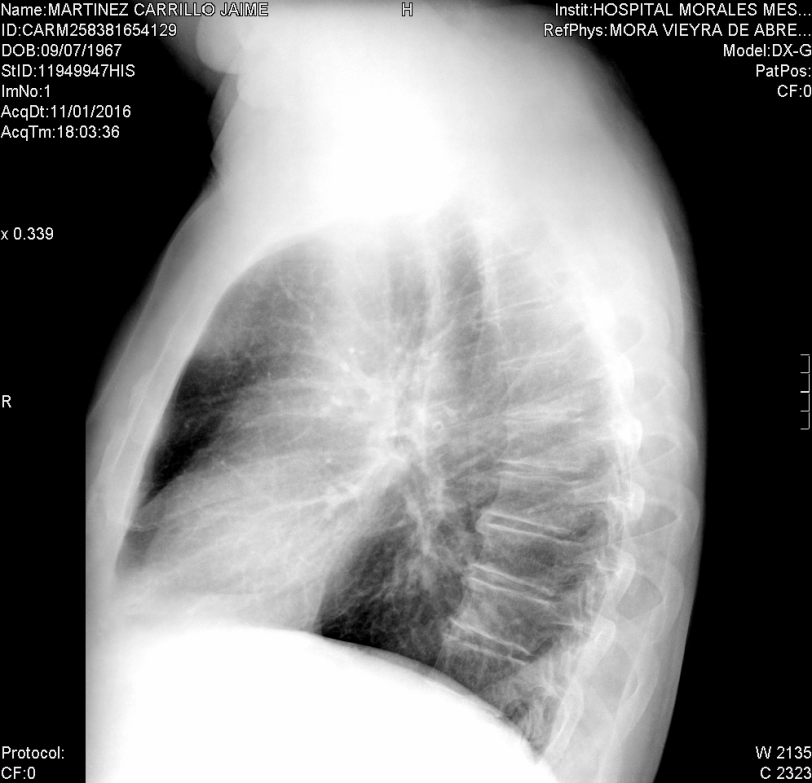

La primera prueba diagnóstica a realizar en un paciente que acude con esta sintomatología es la radiografía de tórax en dos proyecciones: posteroanterior y lateral, en inspiración máxima. Se trata de una prueba poco costosa que le supone poca radiación al paciente y que es sensible a los cambios morfológicos que puedan existir.

Haz click en las imágenes para verlas ampliadas